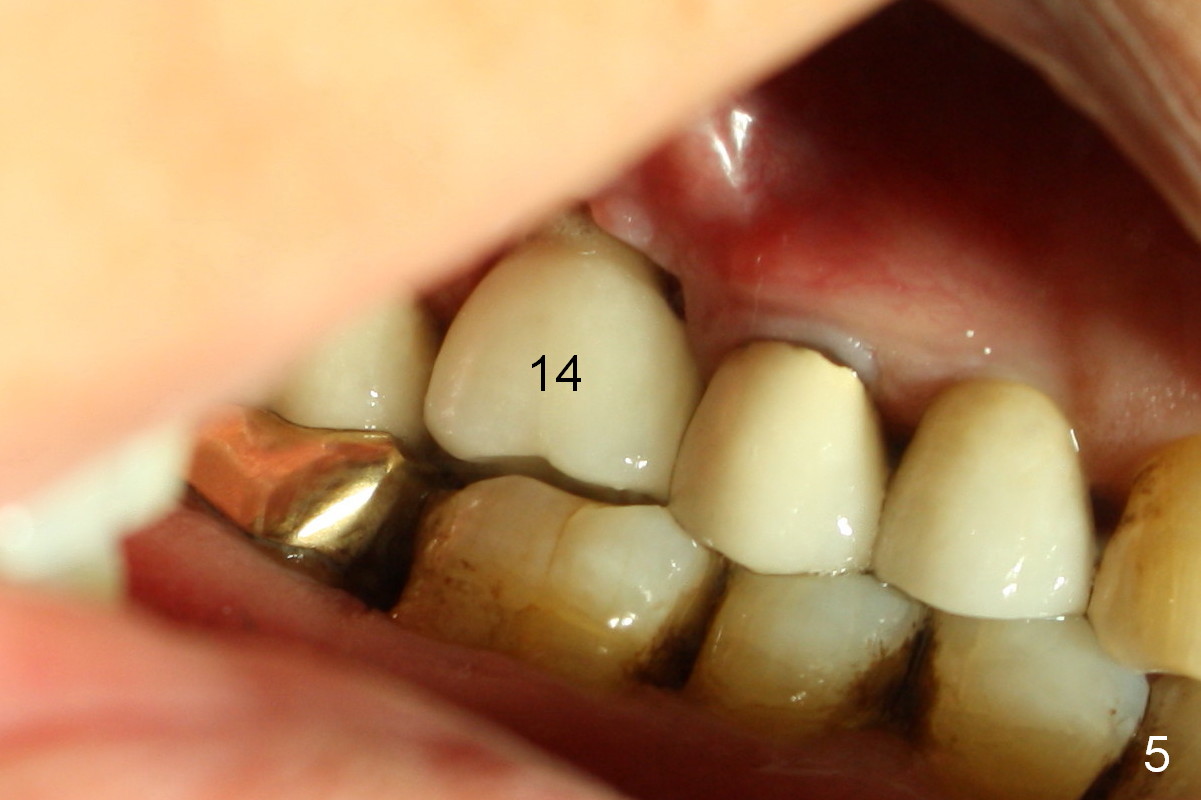

A 73-year-old man returned for recall and had panoramic X-ray taken yesterday. The latter shows no bone loss associated with different types of implants (Fig.1). The implants (relatively small in diameter) and crowns were present at the sites of #3 and 12 when the patient presented to my clinic 6 years ago. His chief complaint was discomfort at #13-15 fixed partial denture (FPD). The tooth #15 seems to be without pathology. To increase its longevity, the FPD was removed (Fig.2), a 5x8 mm Bicon implant (short) was placed at #14 (5 years 11 months post cementation now) and single unit restorations were cemented at #13 and 15 (Fig.3). The occlusal table of the implant crown at #14 is narrow buccopalatally (Fig.4). The occlusal contact of the implant restoration is minimal (Fig.5), which is unfavorable for the weakened tooth (#15). The latter shows sign of failure 7 months post #14 crown cementation (Fig.6 >). The patient refused to accept treatment for #15. Seven months later, the tooth #5 fractured (1st sign of bruxism) and a 5x20 mm cylindrical Tatum tissue-level implant (long) was placed immediately (4 years 5 months in function now). Finally the patient agrees with immediate implant at #15 (7x17 mm tapered Tatum tissue-level implant, large). Follow up is 2 years 7 months post cementation. Ideally 2 implants should have been placed when the FPD was removed. To reduce deleterious effect of bruxism, the last implant was placed with bone expansion at the edentulous area at #2 (5.3x14 mm DIO submerged implant, 1 year 9 months post cementation now). The 2nd sign of bruxism is placement of inlay/onlay on the teeth #19 and 30 (Fig.1). The palatal cusp of the implant crown at #13 remains untreated. The 2 immediate implants at #5 and 15 happen not to have immediate provisional. In all, for a bruxer, an implant does not have to be large or long as long as implant trajectory is correct.